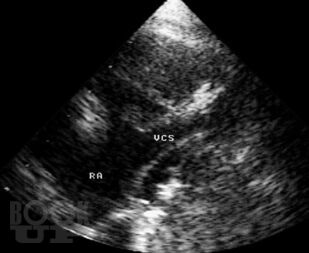

В атласе на большом числе богато иллюстрированных примеров дана эхо- и допплеркардиографическая картина врожденных пороков и ряда заболеваний сердца, а также правила применения методики ультразвукового исследования. Издание восполняет дефицит информации об ультразвуковой диагностике многих сложных врожденных пороков сердца и возможности оценки состояния больных после хирургической коррекции порока.

При подготовке атласа сотрудниками Научного центра сердечно-сосудистой хирургии им. А.Н. Бакулева РАМН (директор – академик РАМН Л.А. Бокерия) использован опыт ультразвукового исследования больных с пороками и заболеваниями сердца (более 60000 пациентов), обследованных в Центре за период с 1976 по 2003 г.